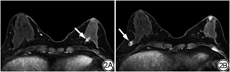

BERGER等[14]、BOISSERIE-LACROIX等[28]认为对于有乳头溢液而乳腺X线摄影及超声检查正常的患者,MRI在识别需要切除的病变方面有很好的性能,MRI正常建议随访是安全的,可避免不必要的导管切除。MRI不需要导管插管,有助于提高患者的舒适度;不仅能观察导管内情况,还可以评估邻近组织、皮肤及淋巴结,多序列、多参数成像及动态增强给良、恶性病变的鉴别提供了更多的信息,在评估乳腺癌侵袭乳头乳晕复合体方面具有高敏感度(90.00%~100.00%)[29]。本研究MRI术前对乳腺癌评价为BI-RADS 5类明显高于GL(6∶3),而且两侧乳房同时成像,有利于与对侧乳房进行比较,本组有1例患者因左侧乳头溢液,MRI不仅观察到左乳的病变,且同时发现右乳有一肿块,病理结果为导管乳头状瘤伴DCIS,因该侧乳腺无乳头溢液而没有纳入本研究病例统计,如果只做GL,右乳病变将会漏诊。MRI对发现导管扩张的能力也与GL相当,本研究两种检查方法发现导管扩张分别为43个和40个,MRI可因导管内液体的性质不同,于T1WI及T2WI显示不同的信号,往往2个序列的信号相反或信号相同,而本组7个恶性病变均显示了这种异常信号的导管扩张。当然,本研究病例MRI是晚于GL所做,GL的图像解读会给MRI的判断提供参考,两种检查均未在同一天进行,GL所使用的对比剂不会给MRI信号造成影响,本研究注意到,GL显示充盈缺损的区域,MRI往往发现肿块样强化。